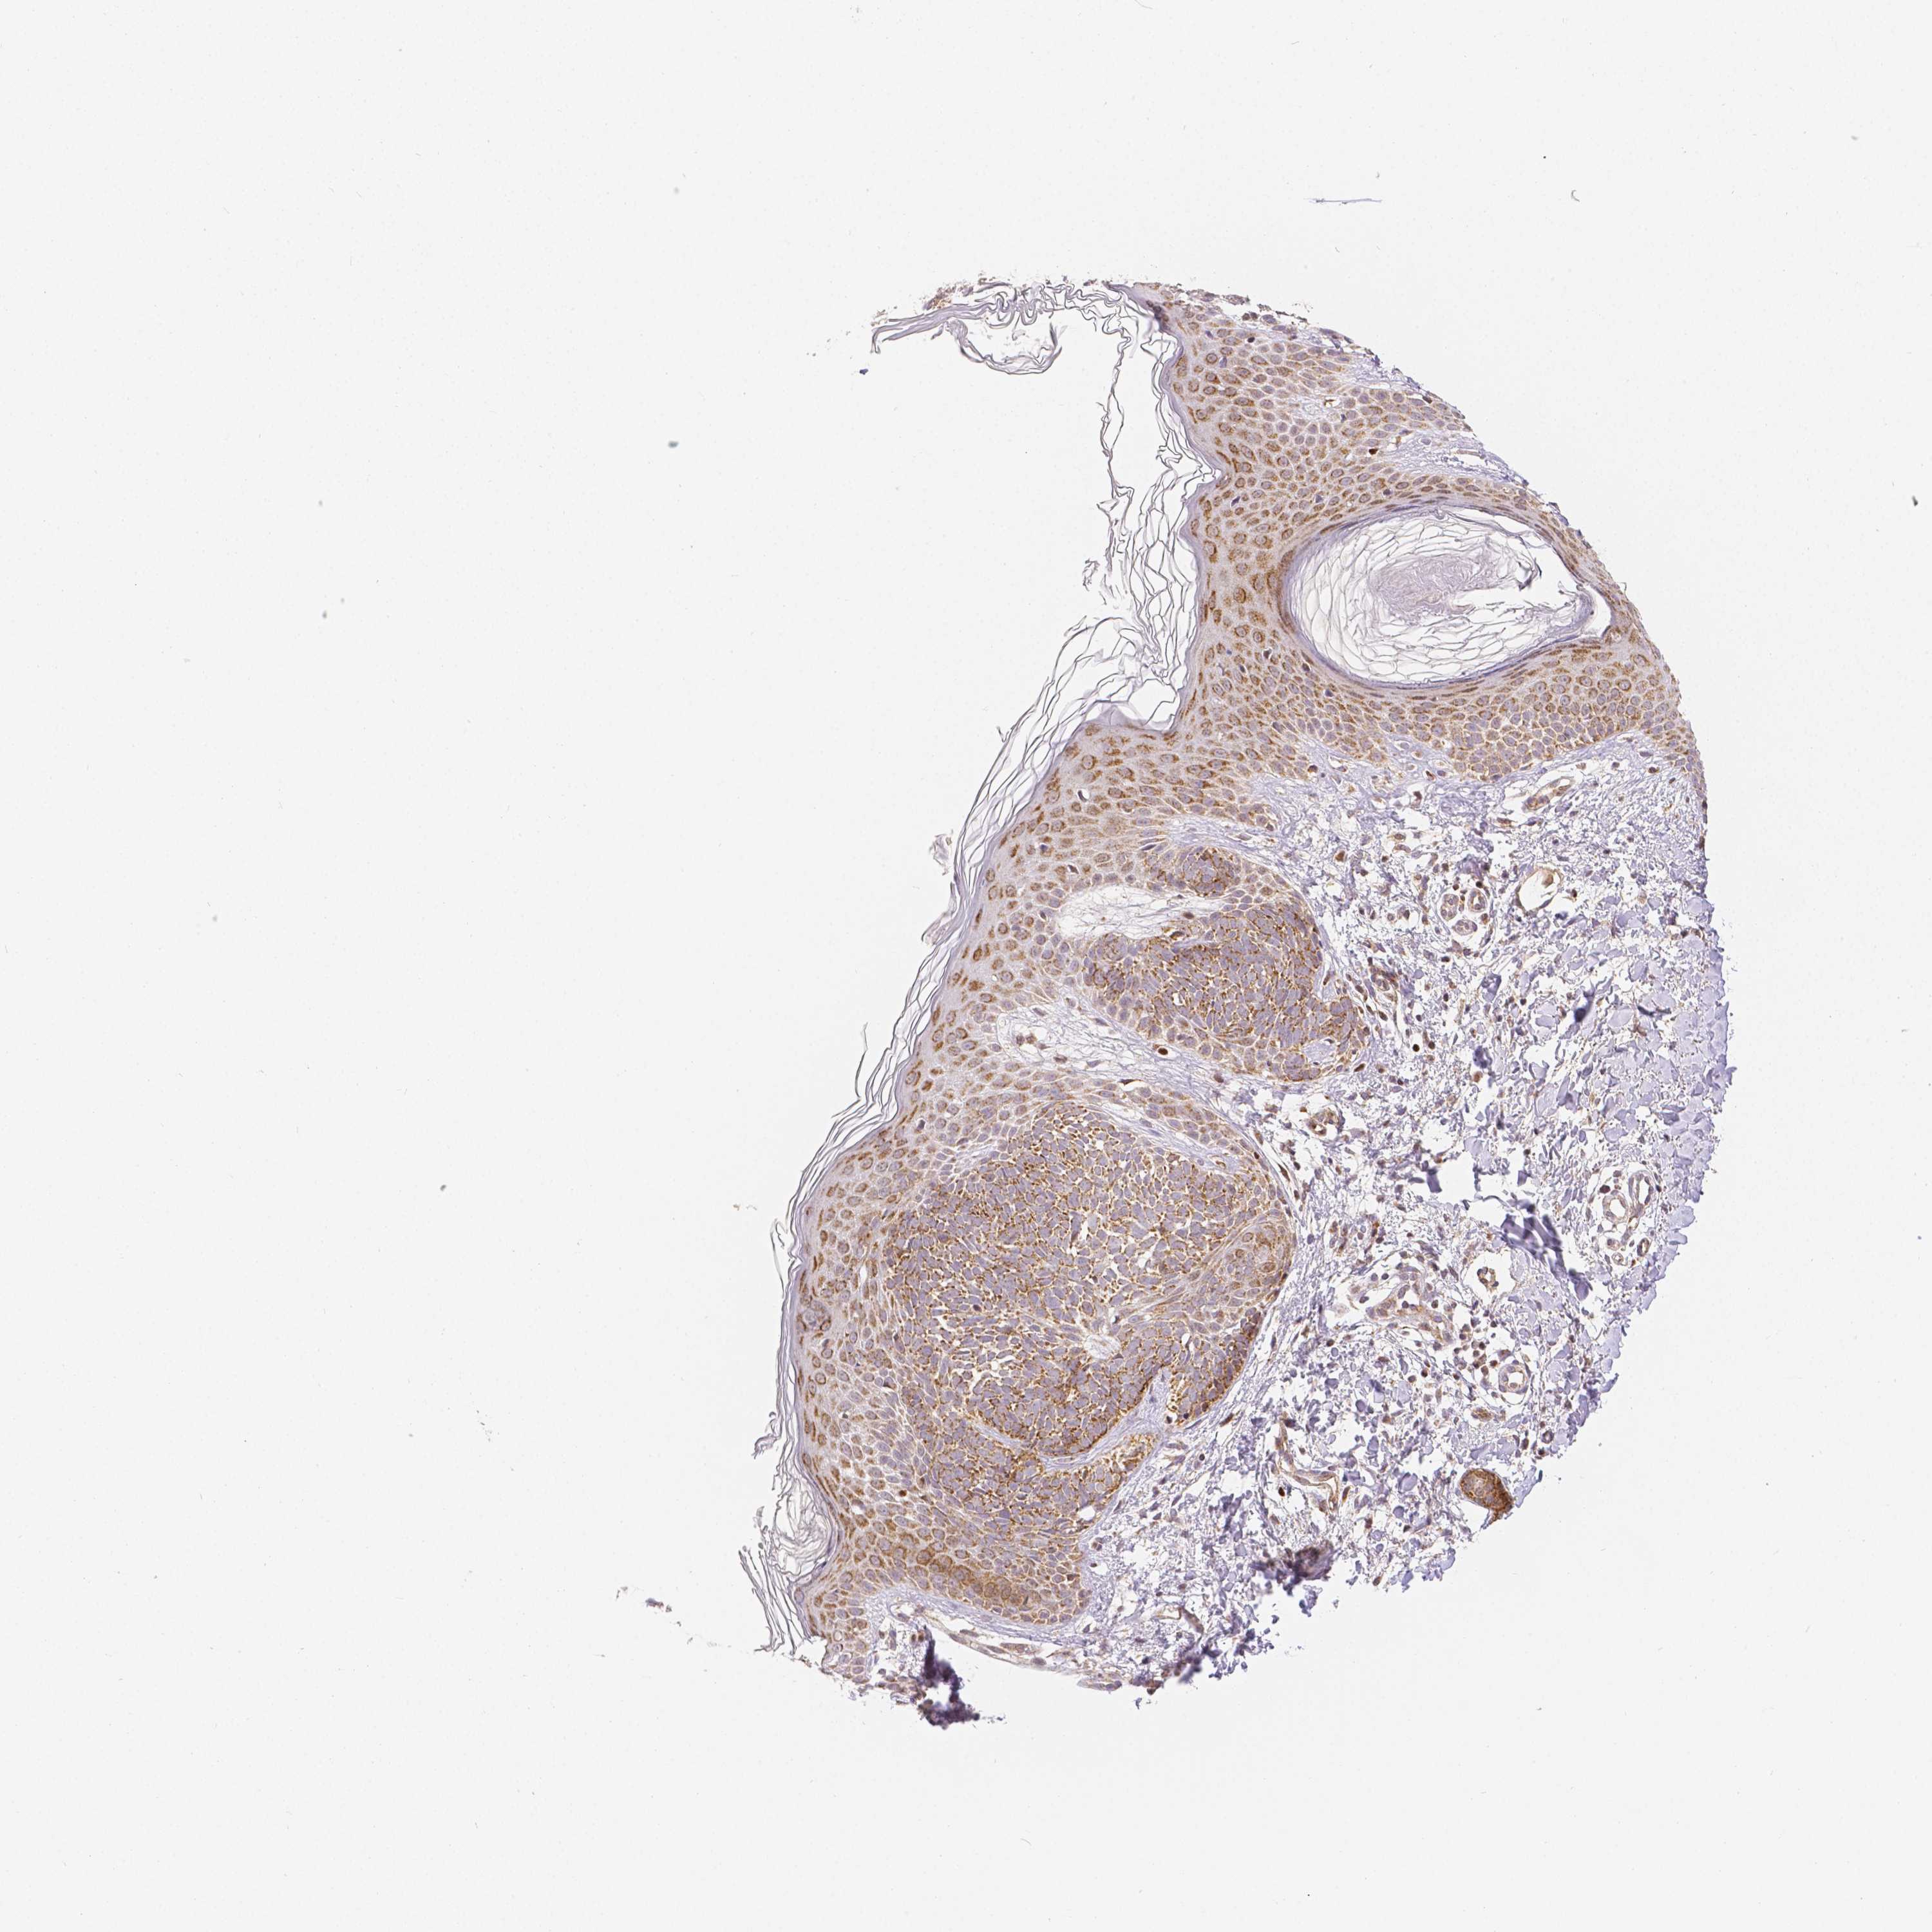

SKIN CANCER - Protein expressioni

A mouse-over function shows sample information and annotation data. Click on an image to view it in a full screen mode. Samples can be filtered based on level of antibody staining by selecting one or several of the following categories: high, medium, low and not detected. The assay and annotation is described here.

Each image is clickable and will lead to virtual microscopy that enables deeper exploration of all samples and also displays staining intensity scores, fraction scores and subcellular localization as well as patient and tissue information for each sample.

Antibody HPA010687

Staining

High

Medium

Low

Not detected

Intensity

Strong

Moderate

Weak

Negative

Quantity

>75%

75%-25%

<25%

None

Location

Nuclear

Cytoplasmic/membranous

Cytoplasmic/membranous,nuclear

Squamous cell carcinoma, NOS

Squamous cell carcinoma, metastatic, NOS

Basal cell carcinoma

Papilloma, NOS